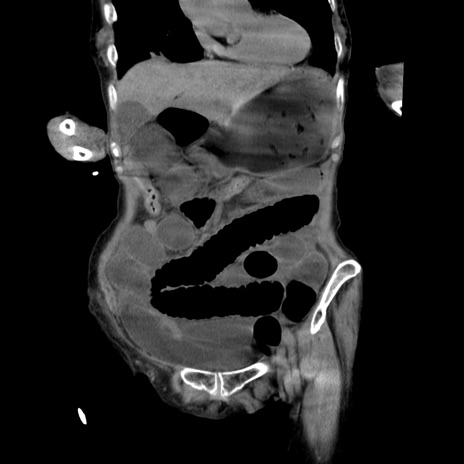

症例27(冠状断像)

【症例】80歳代女性

【主訴】嘔吐、腹痛

【現病歴】数時間前より嘔吐あり。心窩部痛出現し、徐々に右下腹痛あり。その後も数回嘔吐あり救急搬送となる。

【既往歴】左大腿骨頚部骨折手術

【身体所見】腹部は膨隆しているが軟らかく圧痛なし。腸雑音はやや亢進。

【データ】WBC 12000、CRP 19.05